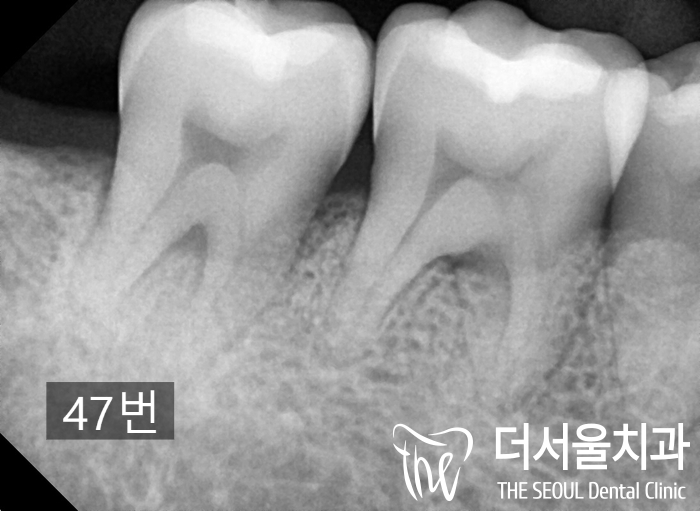

내부에도 진행된 병소로 인해

치수 부근까지 심하게 썩어있었습니다.

미리 찍어둔 X-ray 사진을 같이 보여드렸습니다.

작업을 하며 중간에 엑스레이를 촬영하여

한번 더 제대로 수복이 되었는지 체크를 하게 되며,